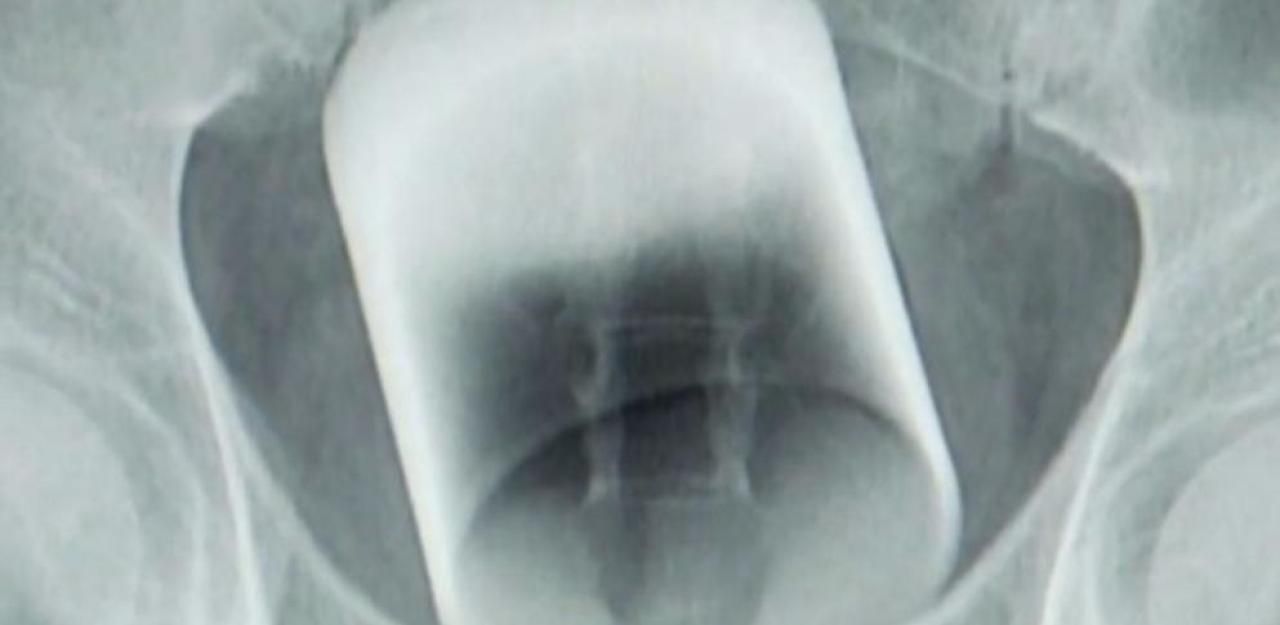

Ärzte finden 7-cm-Glas in Patienten-Po